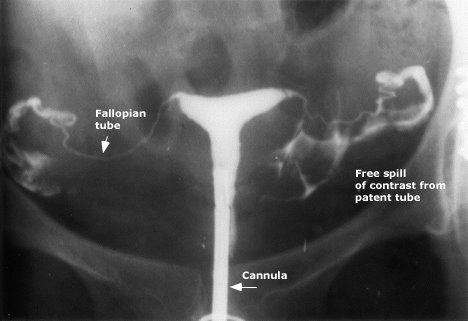

Meme mr ı çekilmesi için en ideal zaman adet döngüsünün başlamasının 7 ila 10. çünkü bu dönemde rahim dokusu daha ince olduğundan ötürü incelemeler adına daha sağlıklı kararlar alınmakta ve değerlendirmeler yapılmaktadır. Histerosalpingorafi hsg genellikle adet kanaması bittikten sonra birkaç gün içerisinde çekilir. çekim işlemlerinin ne zaman yapılacağı en doğru şekilde tespit edilmelidir.